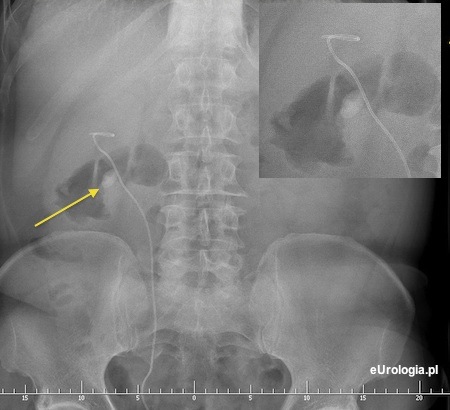

Kamica resztkowa dolnego kielicha po ESWL złogu w miedniczce nerkowej

Kruszenie dużego kamienia w nerce ESWL może być nieskuteczne i często wymaga leczenia uzupełniającego - ponowne ESWL lub PCNL. Czasami konieczne jest endoskopowe usunięcie fragmentów złogu z moczowodu - URS. W Pańskim przypadku część fragmentów rozkruszonego złogu wpadła do dolnego kielicha nerki dając obraz kamicy resztkowej. Nie jesteśmy w stanie odpowiedzieć czy złóg z miedniczki został w całości usunięty - rozkruszony. Poniżej może Pan zobaczyć przykładowe zdjęcia pacjenta z kamicą resztkową po ESWL.